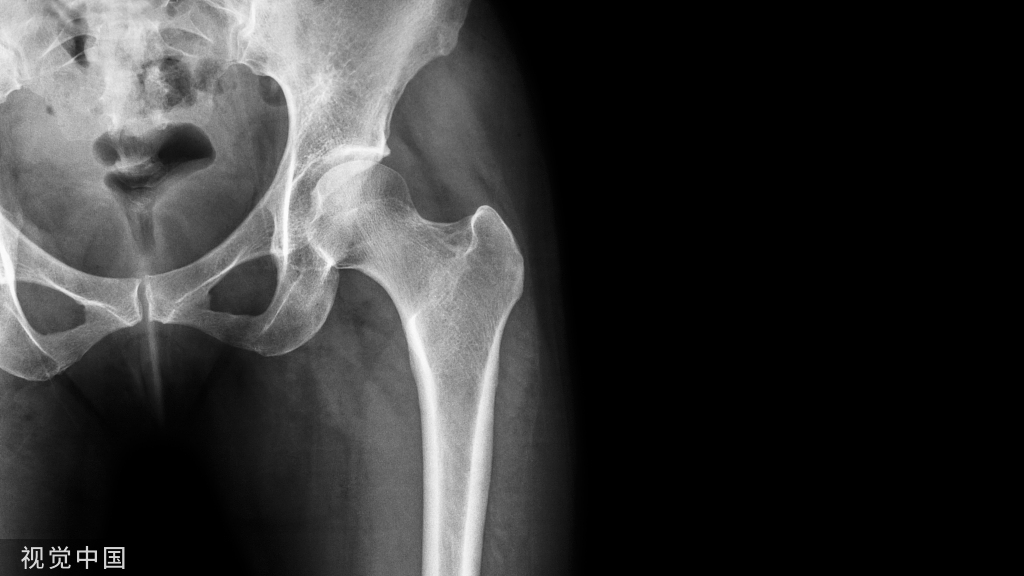

显微镜通道/内镜下进行后路椎间孔切开减压术是治疗神经根型颈椎病的一种微创非融合术式。

显微镜通道/内镜下进行后路椎间孔切开减压术是治疗神经根型颈椎病的一种微创非融合术式。多节段脊髓型颈椎病合并神经根型颈椎病时,可采取后路单开门椎管成形+椎间孔切开减压术。无论通道下、内镜下或单开门同时进行椎间孔切开减压,主要手术操作是相似的。下面文献作者采用的是通道辅助显微镜下手术,安装通道并使用显微镜后主要操作步骤如下: